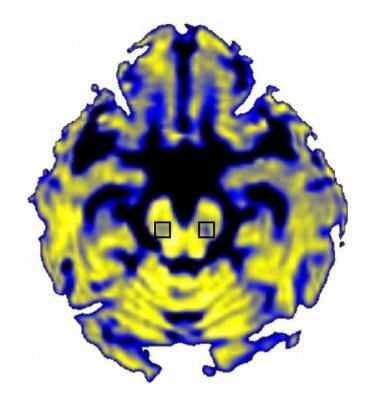

NIH-funded scientists have discovered that Parkinson’s disease increases the amount of “free” water in a particular brain area. Image courtesy of David Vaillancourt, Ph.D., University of Florida.

The researchers, led by David Vaillancourt, Ph.D., a professor of applied physiology and kinesiology at the University of Florida in Gainesville, FL, used a form of MRI that differentiates between water contained in brain cells and “free” water outside of cells. Their analysis focused on the substantia nigra, a brain structure where Parkinson’s disease kills neurons that use the chemical dopamine to communicate with other cells. The results showed that the amount of free water in that brain area stayed the same over the course of a year in healthy individuals but increased in early-stage Parkinson’s patients during that period and increased further over the next three years. This confirms and expands on a prior study by the same group that measured free water over just one year. The new findings also revealed the increase in free water was linked to worsening symptoms.